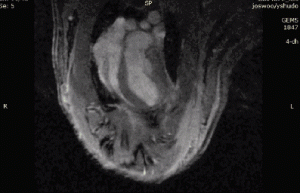

隨后,研究人員開(kāi)始在活體動(dòng)物身上進(jìn)行對(duì)照實(shí)驗(yàn):他們?yōu)樾∈筮M(jìn)行了開(kāi)胸手術(shù),人為阻斷心臟血液供給來(lái)模擬心臟病發(fā)時(shí)的狀況。此時(shí),再將藻類注入小鼠心臟并進(jìn)行光照,效果是顯著的,藻類產(chǎn)生的氧氣馬上被缺氧的心肌細(xì)胞吸收。

只過(guò)了僅僅?10 分鐘,在光照環(huán)境中的心臟部分的氧氣就增加了?25 倍,而與之對(duì)應(yīng)的仍處于黑暗環(huán)境中的心臟部分的氧氣只增加了?3 倍。

45 分鐘左右,拿只接受光照但沒(méi)注入藻類與只注入藻類但沒(méi)接受光照的心臟進(jìn)行相比,同時(shí)接受藻類和光照的小鼠心臟的供血量分別增加了60%和30%。